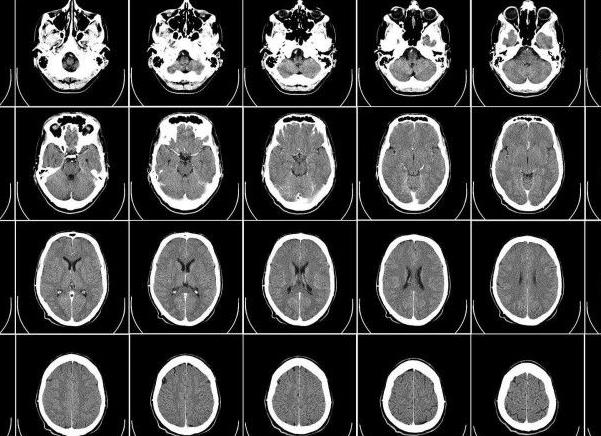

С помощью магнитно-резонансной томографии выявляют нарушения в мягких тканях. Рентген-аппарат определяет травмы и опасные внутренние кровотечения. Первое устройство отличается от второго возможностью представления изображения в трехмерном виде. Чтобы получить изображение в разных плоскостях с помощью рентгена, потребуется многократное рентгеновское облучение. В основе рентгена находятся электромагнитные высокочастотные волны. Они эффективны для диагностики пневмонии, отека и рака легких. Томография работает за счет магнитного поля, с помощью которого специалисты отличают нормальную ткань от патологической. Разница между рассматриваемыми устройствами заключается в том, что МРТ не применяет ионизирующее излучение. Подробнее ...